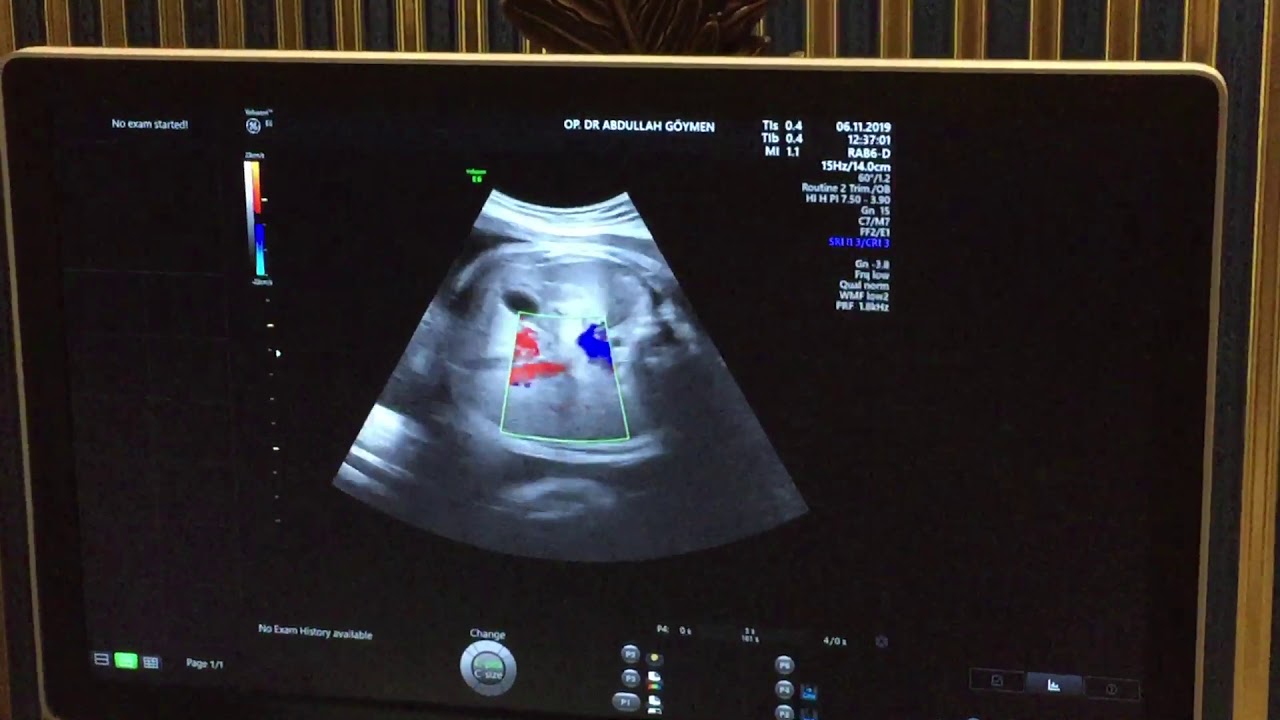

Ultrasonda Gebelik Kesesi Ne Zaman Görünür? Ay Ay Örnek